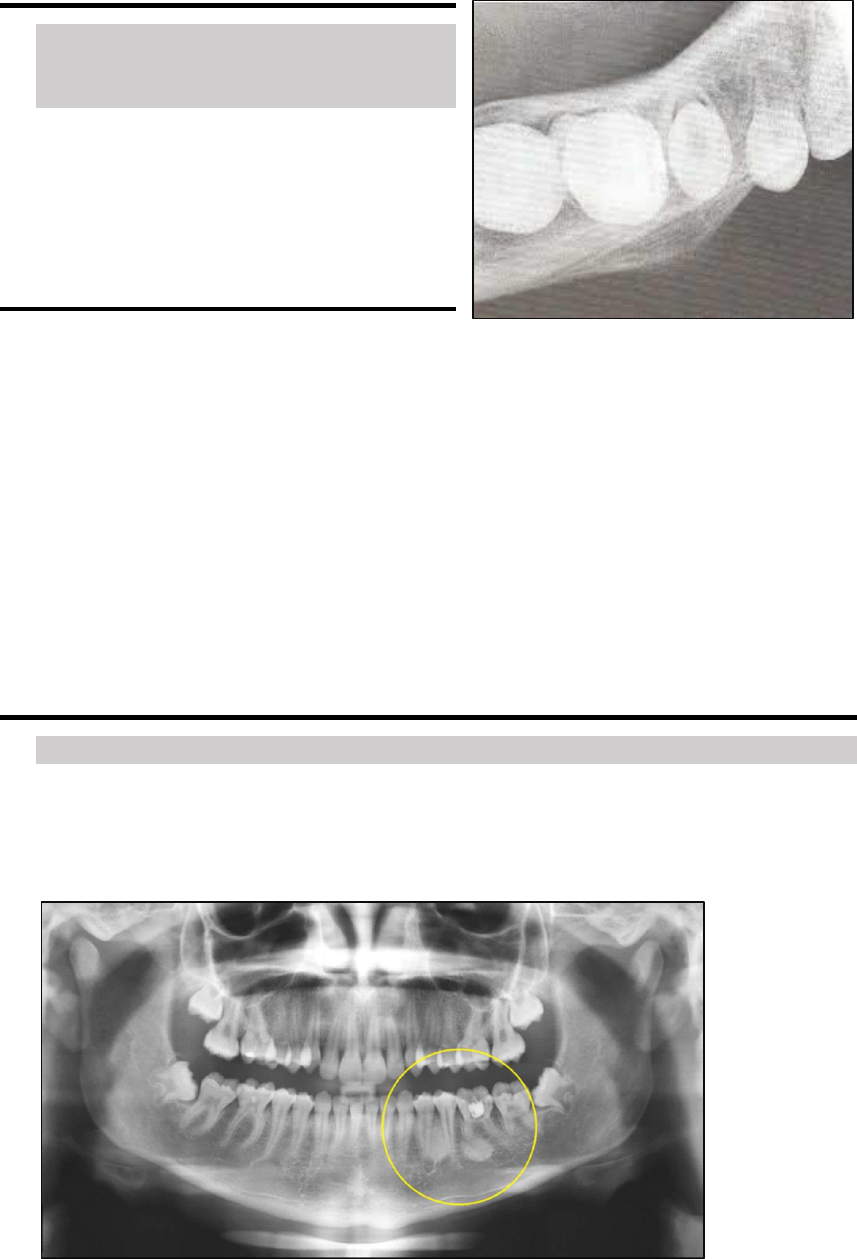

Grátis: AULA 07 Osteomielite (PARTE II) e lesões potencialmente malignas - Material Claro e Objetivo em PDF para Estudo Rápido

Grátis: Osteomielites - Supurativa, aguda, crônica, esclerosante, difusa, focal, pericetite proliferativa - Material Claro e Objetivo em PDF para Estudo Rápido